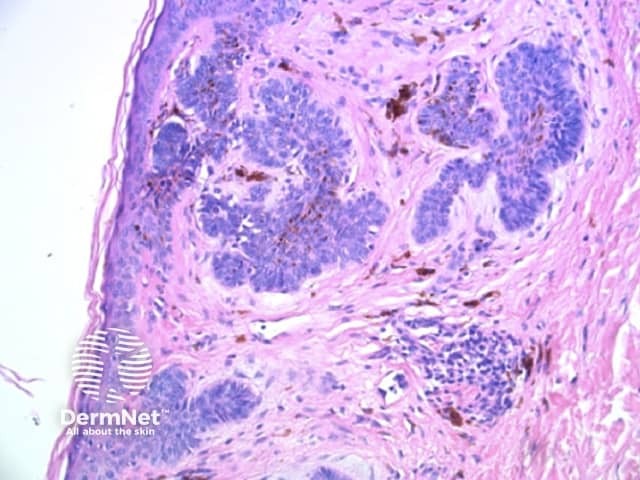

Clods are solid rounded structures of sufficient size to show an appreciable variability in size. Their colour depends on the nature and, in the case of melanin, depth of the substance they comprise (Figures 37-50). Other terms have been used for clods in specific settings such as blue-grey ovoid nests for grey and / or blue clods seen in basal cell carcinoma.

Figure 48. Diagram. Brown, grey and blue clods are due to nests of melanin-containing cells at different levels in the skin. From Kittler et al (1).

Figure 49a Figure 49b Figure 49c Figure 49d

Figure 50a Figure 50b